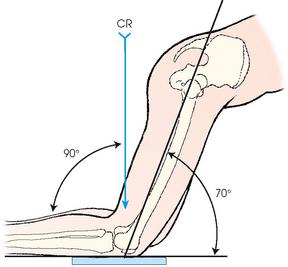

• For all positions, place the IR against the anterior surface of the patient’s knee, and center the IR to the apex of the patella. Flex the knee 70 degrees from full extension (20-degree difference from the central ray, as shown in Fig. 6-138).

Structures shown: The image shows the intercondylar fossa of the femur and the medial and lateral intercondylar tubercles of the intercondylar eminence in profile (Fig. 6-139). Holmblad1 stated that the degree of flexion used in this position widens the joint space between the femur and tibia and gives an improved image of the joint and the surfaces of the tibia and femur.